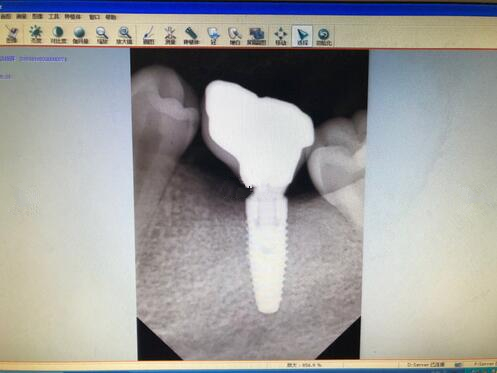

廣州牙齒整形種植牙果圖

現(xiàn)在牙齒已經(jīng)恢復(fù)的相當(dāng)?shù)暮昧?,大家可以看到這幾顆種植牙,看起來(lái)比之前的牙齒都更加好看了呢,而且更加的潔白也結(jié)實(shí)了不少,之前不敢吃的一些食物,現(xiàn)在都可以吃了。